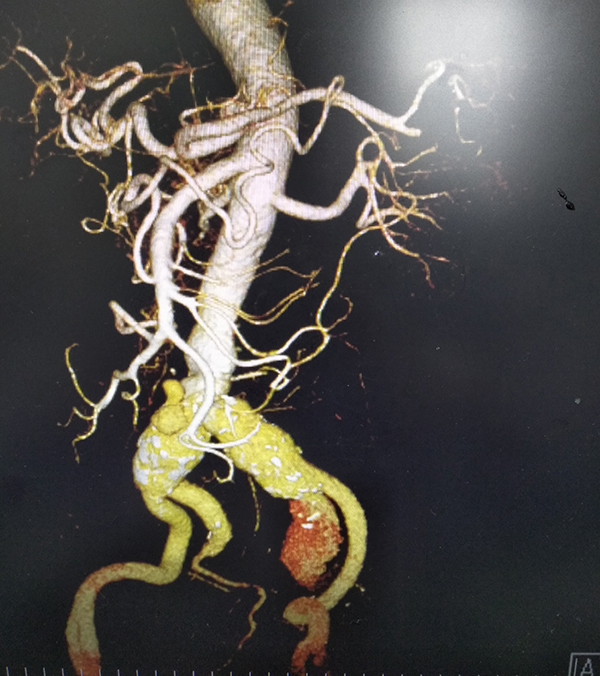

近日,我院胸心血管外科、放射科、介入导管室等多科室合作,成功地为一位患有腹主动脉夹层动脉瘤+双侧髂总动脉瘤+左侧髂内动脉瘤破裂的危重患者施行动脉瘤腔内覆膜支架植入修复术,解除了人体“炸弹”的威胁,及时挽救了患者生命。

72岁的何先生,因下腹部疼痛3天急诊入院,经腹部CTA检查,被诊断为腹主动脉夹层动脉瘤、双侧髂总动脉瘤先兆破裂、左侧髂内动脉瘤破裂,病情极其危重,随时都可能有生命危险。

腹主动脉瘤腔内覆膜支架修复术后 腹主动脉瘤腔内覆膜支架修复术(EVAR)是目前治疗腹主动脉瘤的一种微创外科技术,其手术创伤较小,术后并发症少,使许多不能耐受手术的高危病人获得救治机会。但是EVAR治疗方案十分依赖腹主动脉的解剖学形态,血管腔内操作难度大,技术要求高。这次手术取得圆满成功,标志着我院胸心血管外科在腹主动脉瘤的诊治水平又上了新台阶。(文:韦连素)